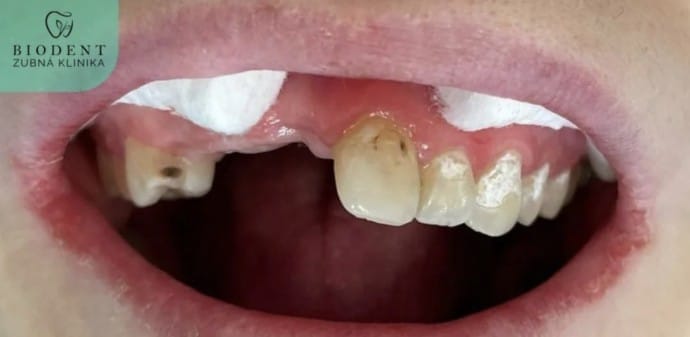

- chýbajúci jeden alebo viac zubov

- zub poškodený kazom viac ako 40%

- Príprava pred nasadením koruniek (ošetrenie kazov, endodoncia a dentálna hygiena)

- Samotná príprava a brúsenie zubov

- Nasadenie dočasných koruniek pre ochranu obrúsených zubov